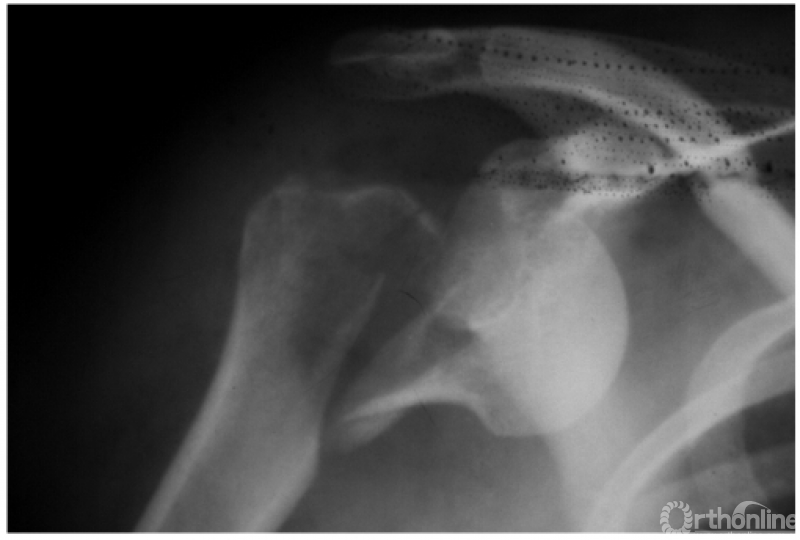

例1:肩关节盂下脱位(如下图)。